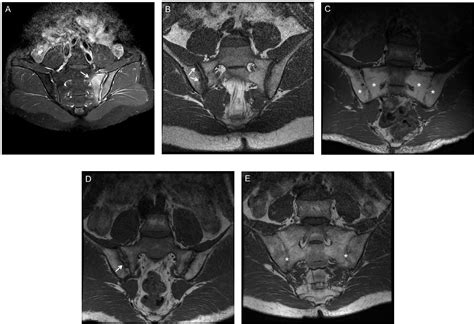

• MRI (Magnetic Resonance Imaging): Superior for detecting soft tissue inflammation, edema, and early signs of sacroiliitis that X-rays miss.

• CT Scan: Offers high-resolution, cross-sectional views of the bone, which can be useful if the X-ray was inconclusive regarding subtle fractures or tumors.

A "negative" result on an Si Joint Xray does not necessarily mean that there is nothing wrong with your sacroiliac joints. As mentioned, X-rays are limited by their inability to visualize cartilage, tendons, or minor swelling. If your pain continues despite a normal X-ray, your physician might recommend more advanced imaging or diagnostic procedures.

It is important to note that while an X-ray is excellent for seeing bone density and structural shifts, it may not reveal soft tissue issues or early-stage inflammation that an MRI or CT scan could detect.